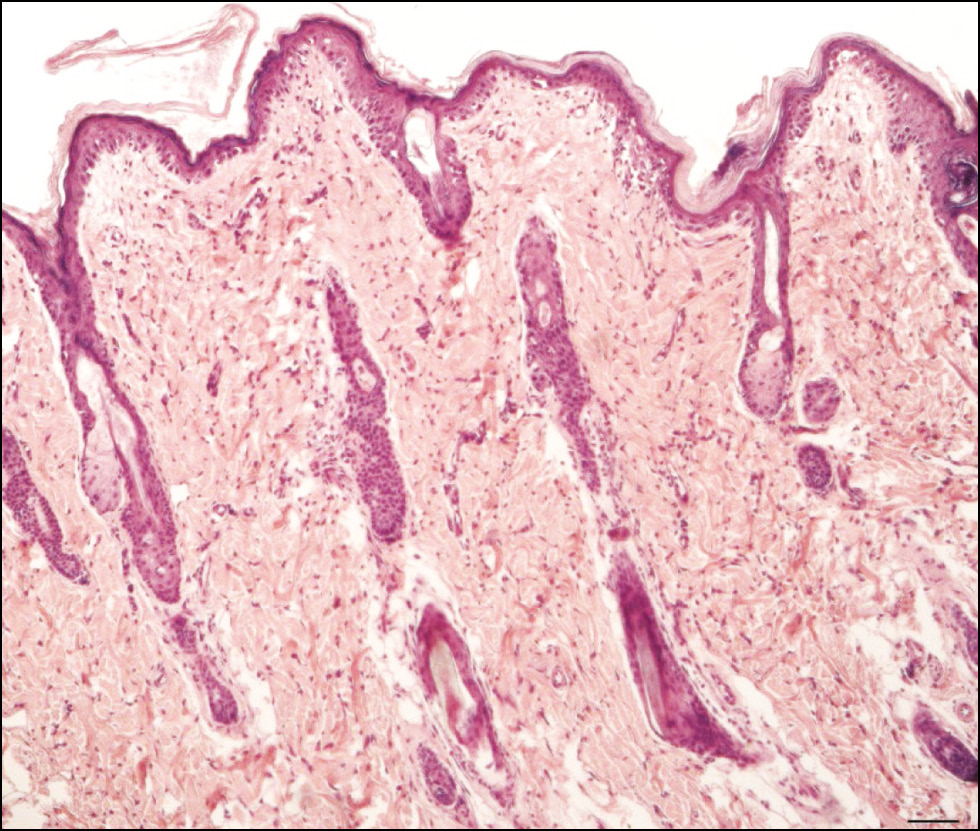

BACKGROUND: The proliferation to apoptosis ratio at a wound site is crucial for healing. Regenerative histogenesis of the skin in the perinecrotic zone is of key interest, specifically the connective tissue layers (the dermis and hypodermis). This zone is characterized by cambial elements of epithelial and connective tissues that drive regeneration, as well as distinctive cell death processes. Immunohistochemical methods are typically used to investigate patterns of histogenetic processes, including proliferation and cell death, in tissues with varying regenerative potential. However, selecting markers that reflect the proliferation to apoptosis ratio at different stages of regeneration remains challenging.

METHODS: An experimental single-center, continuous, controlled, randomized, non-blind study was conducted. Skin samples of the thigh from Wistar rats were obtained at various stages of healing after mechanical injury (deep incised wound). Animals were divided into nine groups: a control group of intact rats (n = 3) and eight experimental groups corresponding to post-injury time points of 12 hours, 24 hours, 2 days, 3 days, 6 days, 10 days, 15 days, and 25 days (n = 3 per group). Tissue fragments were processed for histological and immunohistochemical examination. Antibodies to phosphorylated histone H3 were used to assess proliferation, whereas apoptosis was detected using antibodies to p53 and caspase-3.

RESULTS: Immunopositive cells expressing phosphorylated histone H3, caspase-3, and p53 were identified in cutaneous connective tissue samples in all experimental groups. The proliferation index was determined, and changes in pro-apoptotic protein expression were analyzed in intact skin and the perinecrotic zone at different stages of regeneration. Based on these data, the proliferation to apoptosis ratio and an index characterizing both processes were calculated. The proliferation to apoptosis ratio was highest when proliferation prevailed over cell death (in intact skin and at the final stages of regeneration) and lowest when apoptosis predominated (inflammation and necrosis phases).